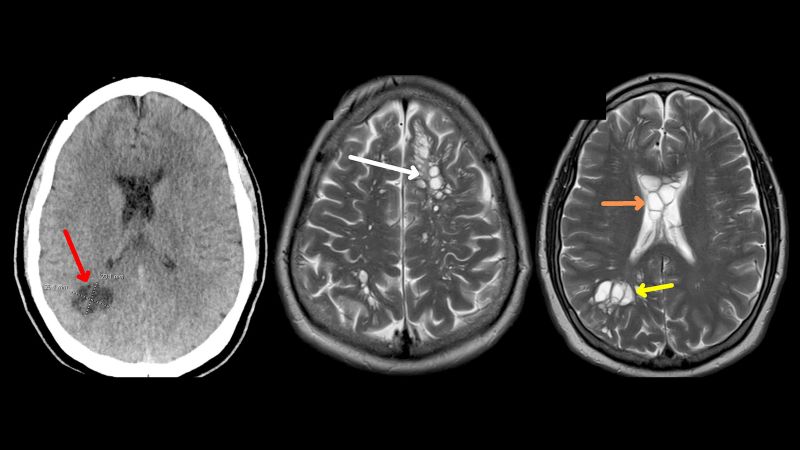

Doctors identify source of man’s migraines: tapeworm larvae, likely from undercooked bacon 🥓, in his brains

A Florida man with worsening migraines was found to have parasitic tapeworm larvae in his brain, according to a report published this month in the American Journal of Case Reports. Doctors believe that the tapeworm infection originated from his habit